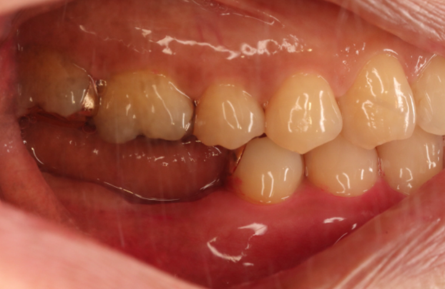

入れ歯の症例

当院で入れ歯治療をされた方の症例をご紹介いたします。

治療前